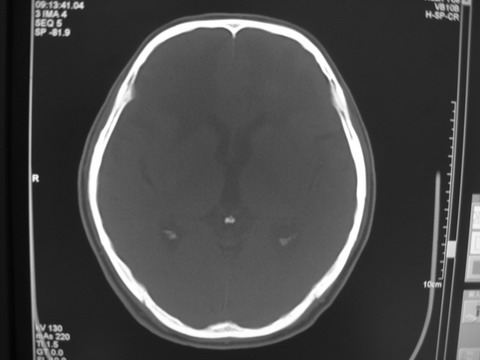

患者 男 69岁 头晕头痛不适

多发病灶,指状水肿,首先诊断转移瘤。

多个结节并周围大面积水肿区,多考虑多发性脑转移瘤

小病灶、大水肿,病灶多发,首先考虑多发转移瘤;建议查原发灶。

额顶叶多发小病灶、大水肿,首先考虑多发转移瘤;建议查原发灶

脑内多发病灶,小病灶,大水肿。

典型转移性肿瘤。

应进一步检查,查找原发病灶。

结果 : 该患者结肠癌病史5年 考虑脑转移